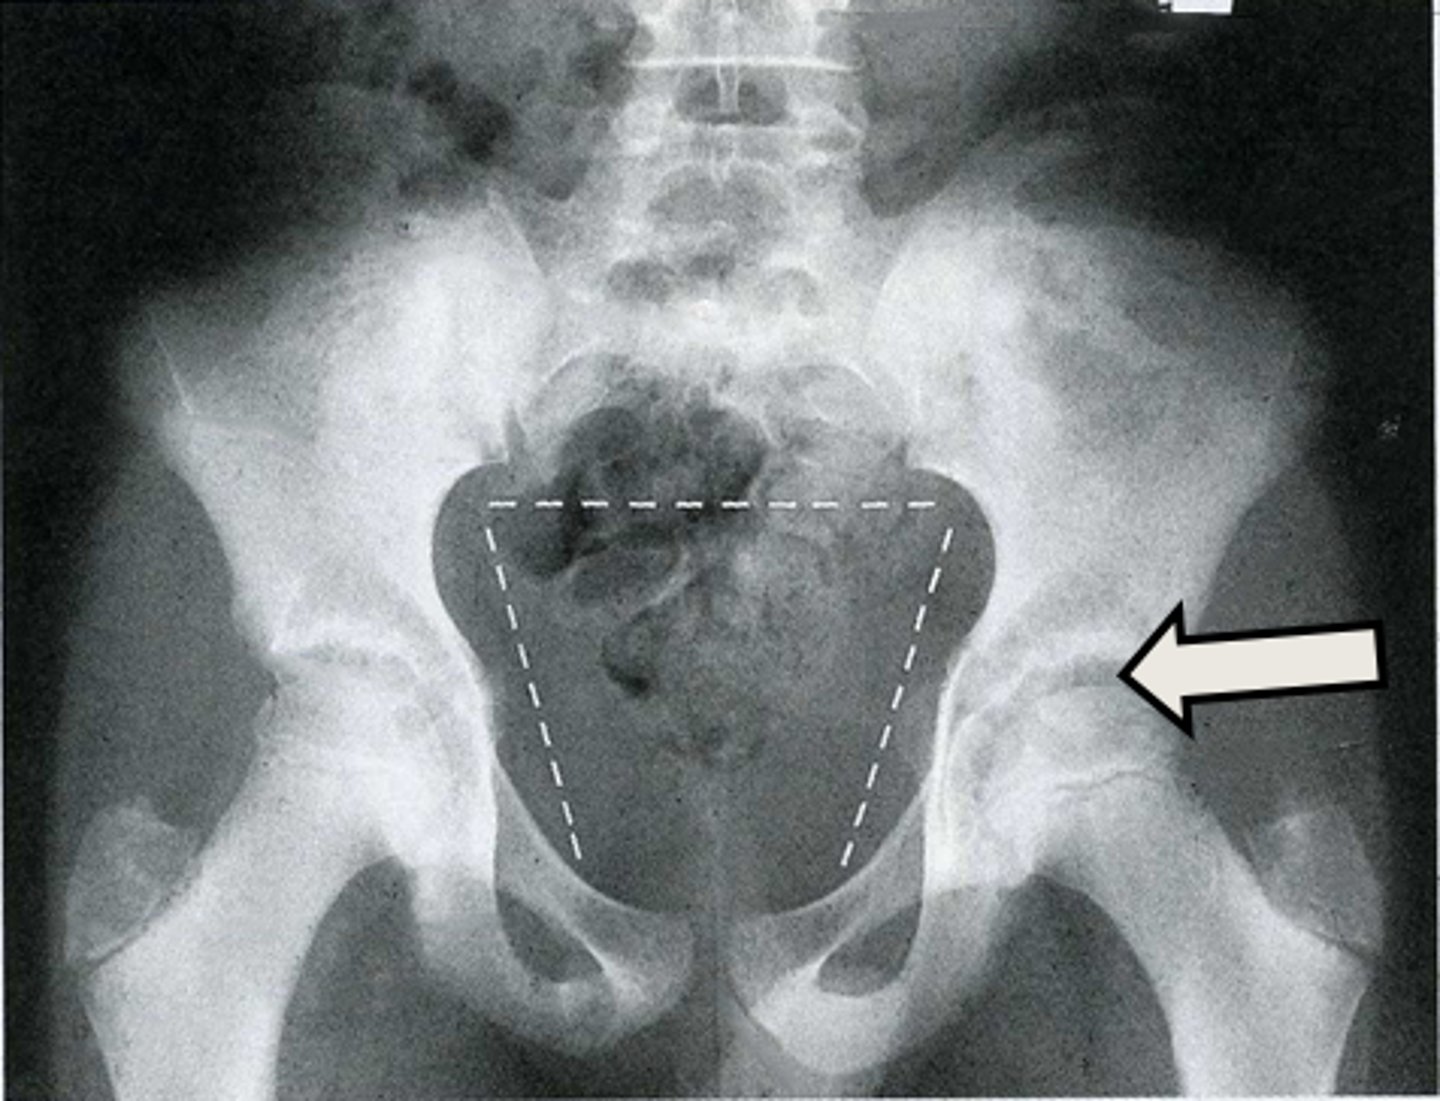

AP pelvis

What is the image?

16

L acetabulum

What is indicated in the image?

17

L anterior superior iliac spine (ASIS)

18

L ilium

19

L ischial tuberosity

20

L obturator foramen

21

L sacroiliac joint

22

L superior ramus of pubis

23

R acetabulum

24

R anterior superior iliac spine (ASIS)

25

R ilium

26

R ischial tuberosity

27

R obturator foramen

28

R sacroiliac joint

29

R superior ramus of pubis

30

Sacrum

<p>What is indicated in the image?</p>